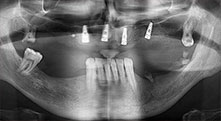

Bratu: Wir nutzen die Instrumente routinemäßig für die Entnahme von Knochenblöcken und das Spalten von Kieferkämmen. Weiterhin osteotomieren wir mit den Piezomed B6/B7 retinierte Zähne und entfernen nicht erhaltungsfähige Implantate. Alles Indikationen, bei denen es auf tiefe, saubere Schnitte ankommt.

Bratu: Wir bevorzugen Knochenentnahmen von der Linea obliqua externa des posterioren Unterkiefers, nicht aus der interforaminalen Region. Nach der Weichgewebsinzision verwenden wir die neuen Sägen, um den Umfang der Knochenentnahme zu definieren. Wir erledigen damit in fast 80 Prozent der Fälle auch die gesamte Präparation. Zusätzlich verwenden wir eventuell andere Piezo-Instrumente und zuletzt einen Meißel, um den Block zu mobilisieren. Das ist für uns eine sehr effektive Operationstechnik.

Bratu: Wir augmentieren im seitlichen Unterkiefer gern mit der Sandwich-Technik. Dabei wird ein Knochendeckel mit der Piezosäge präpariert und das krestale Fragment mit Mikroschrauben fixiert. Dazwischen platzieren wir eine Mischung aus autologem Knochen und xenogenem Knochenersatzmaterial. Das funktioniert sehr zuverlässig. Bei Kieferkammspaltungen im Unterkiefer sollten Sie nie auf ausreichend dimensionierte vertikale Schnitte verzichten. Sonst kann der Knochen leicht frakturieren.